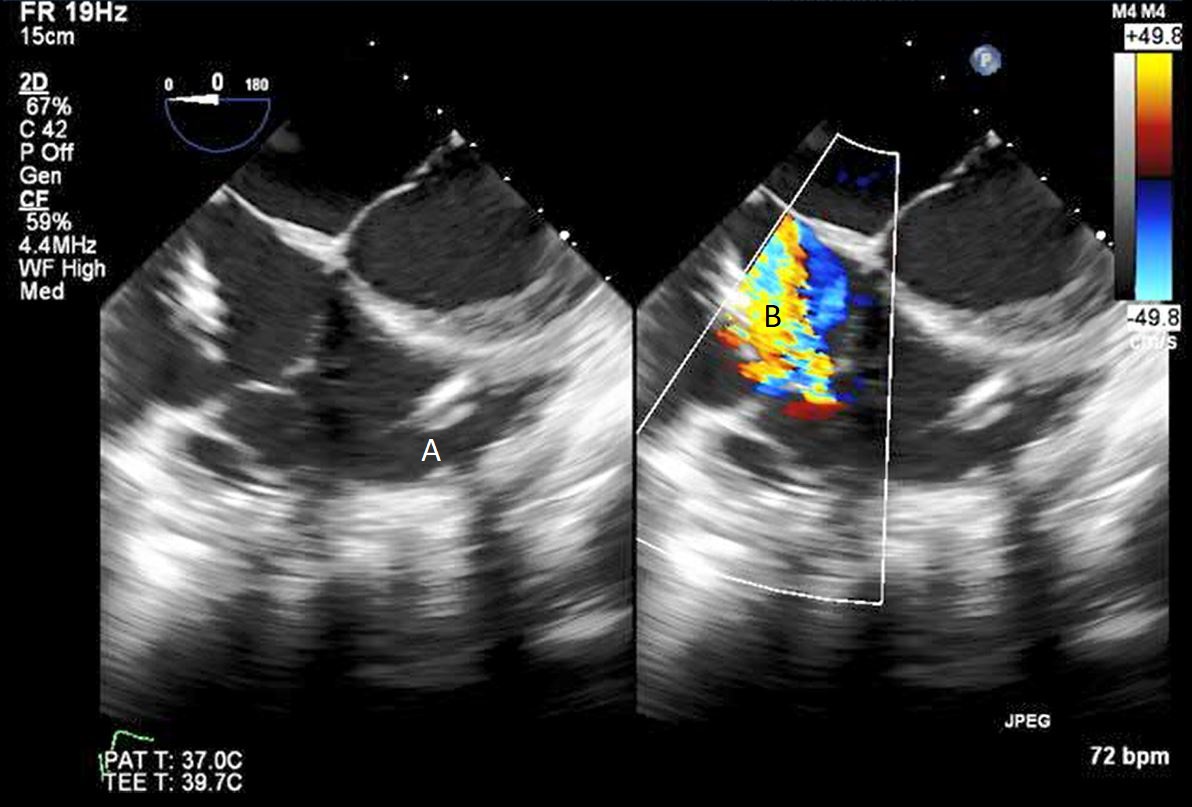

The TandemHeart Protek Duo is a percutaneous right ventricular assist device (RVAD) placed via a dual-lumen 29 French sheath in the right internal jugular vein. The inflow lumen is situated in the right atrium and outflow lumen in the main pulmonary artery. The port lumens are connected externally to a TandemHeart centrifugal pump [31]. As this is generally placed in the operating room, intra-operative TEE can be used to help guide placement. Similar to the Impella RP, bicaval and midesophageal 4 chamber views can visualize the inflow cannula and RV inflow-outflow view and upper esophageal views can be used to visualize the outflow cannula (Figs. 13,14,15). On occasion, its placement can result in distortion of the tricuspid valve morphology with resultant tricuspid regurgitation (Fig. 16). If this is noted, cannula repositioning can be considered. TEE can also help in identifying the ideal pump speed for a patient on TPD support. When utilizing a “ramp protocol”, where the pump speed is progressively increased intraoperatively, midline interventricular septal position can indicate an appropriate amount of RV support [32].

Protek Duo (A) visualized in RV. Its placement caused disruption of tricuspid valve with resultant tricuspid regurgitation seen on color flow imaging (B).